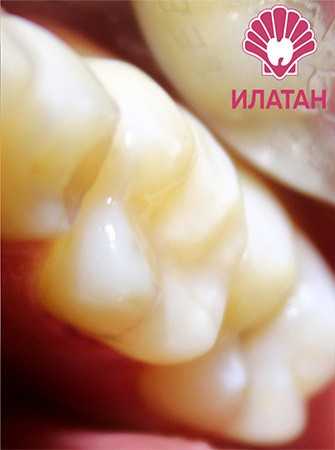

19 работ в портфолио

Щербакова (Полякова) Анна Сергеевна принимает в сети семейных стоматологических клиник ИЛАТАН в Москве. Стаж 11 лет. Специализируется на детской стоматологии и эндодонтическом лечении, по которым клиника оказывает 14 услуг. Имеет 19 работ до/после в портфолио. Квалификация специалиста подтверждена 21 лицензиями, сертификатами и наградами, а опыт 13 отзывами пациентов, из которых 13 положительные. Для уточнения дополнительной информации о специалисте или записи на прием можно позвонить по телефону